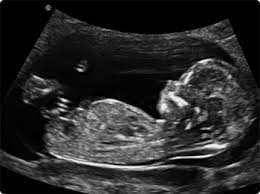

The median age at death is now the mid-50s compared. Down syndrome varies in severity among individuals causing lifelong intellectual disability and developmental delays. You may have an ultrasound between 18 to 20 weeks to evaluate dates a multiples pregnancy placenta location or complications.

The 20-Week Anatomy Scan May 2017.

Down syndrome is a genetic disorder caused when abnormal cell division results in an extra full or partial copy of chromosome 21. This test is done between 15 and 20 weeks of pregnancy. In 2011 a nicely done experiment by Marshall et al showed that regular hamstring stretching substantially increased range of motion in normal university kids95 Specifically after a 4-week stretching program consisting of 4 hamstring and hip stretches performed 5 times per week their range increased about 16 or 20. Down syndrome is a genetic disorder caused when abnormal cell division results in an extra full or partial copy of chromosome 21. In Down syndrome the nuchal translucency measurement is abnormally large as shown on the left in the ultrasound image of an 11-week fetus. How is a dating scan performed. The 20-Week Anatomy Scan May 2017.